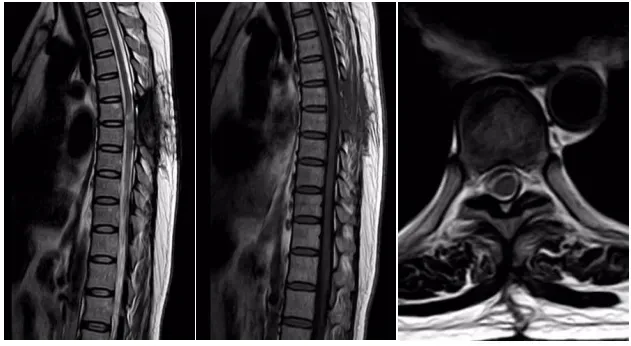

一位女性患者,11个月前没有明显诱因出现双下肢麻木、无力症状,同时伴有排便无力和间歇性跛行的情况,当时并未引起重视。一段时间后,病情逐渐加重,10天前竟严重到无法行走。为寻求治疗,患者来到我院脑外科就诊。门诊通过胸椎 MRI+增强检查发现,胸6-7椎管内左缘髓外硬膜下富血供肿瘤,再结合CT检查后,考虑脊膜瘤,于是以“椎管内占位性病变”将患者收入脑外科住院治疗。

入院后,脑外科团队积极开展术前准备工作。经过详细诊断,基本确定为椎管内肿瘤,脊膜瘤的可能性最大,决定为患者实施肿瘤切除术。术中可见肿瘤呈砂砾状,大小约1.5×2.2cm,颜色呈灰白色,血供丰富且质地坚韧,相应位置的硬脊膜增厚,脊髓受压明显且向右移位,不过幸运的是,肿瘤与脊髓并无明显粘连。在显微镜下,医护人员小心翼翼地将肿瘤分离,严密保护脊髓,最终分块将肿瘤完全切除,病理诊断结果为脊膜瘤。患者恢复良好,现已顺利出院。